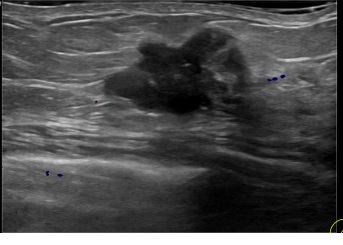

아산유외과개원후 842번째 유방암진단

상기환자는 외부검사이상 조직검사위해 내원하신 50대후반

여성분으로 의심스러운 좌측혹 조직검사 시행해 유방암 진단되었습니다